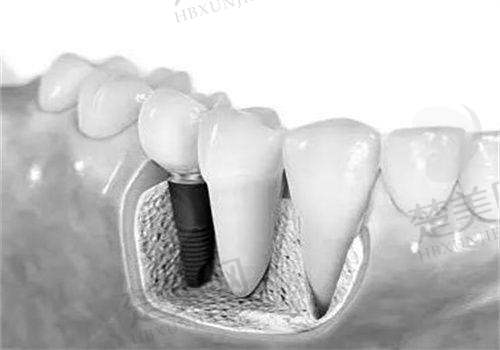

上海新菲口腔的种植牙技术主打“快、准、稳”,下面给大家详细介绍。

3D数字化导板:通过CBCT扫描和口内3D建模,能把误差控制在0.1mm内。单颗种植仅需10分钟,还能避开血管神经。

微创不翻瓣:采用2 - 3mm的微小切口,全程可视化操作,术后不会肿胀疼痛,第二天就能正常上班。